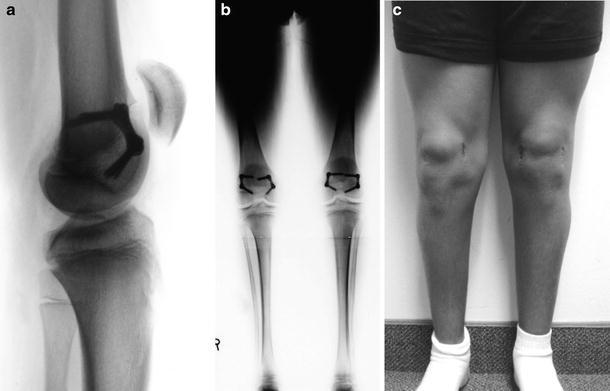

Fig. 3.

a Lateral view documenting full correction of the fixed knee flexion deformity. Despite the residual patella alta, he has no pain, patellar instability, or related functional limitations; therefore, the patellar tendon does not need to be advanced. b A full-length radiograph showing the retained 8-plates. c Clinical appearance at the time of follow-up gait analysis. Upon full correction of the fixed knee flexion deformity, the 8-plates are typically removed. All images are from subject 1